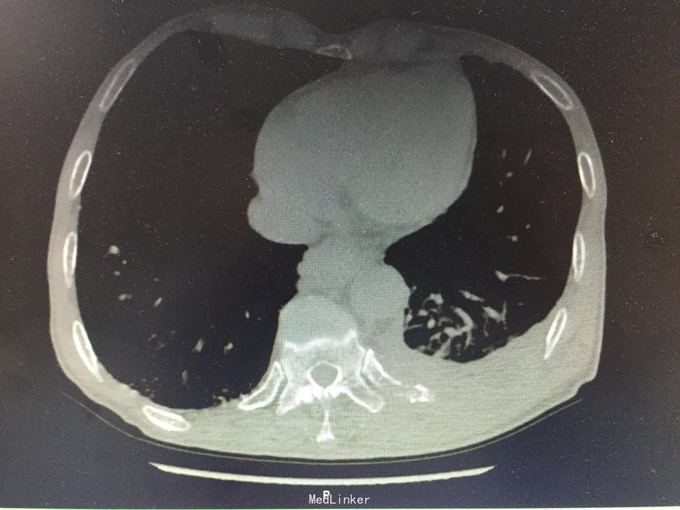

MRI示:肋骨,胸椎多发骨转移 CT示:胃Ca术后:腹膜后淋巴结转移,左侧胸膜多发转移,左侧后壁转移并T10锥体及左侧横突,第10.11后肋转移骨质破坏,骨质疏松并T12及L2压缩骨折 核医学ECT示:多发骨转移